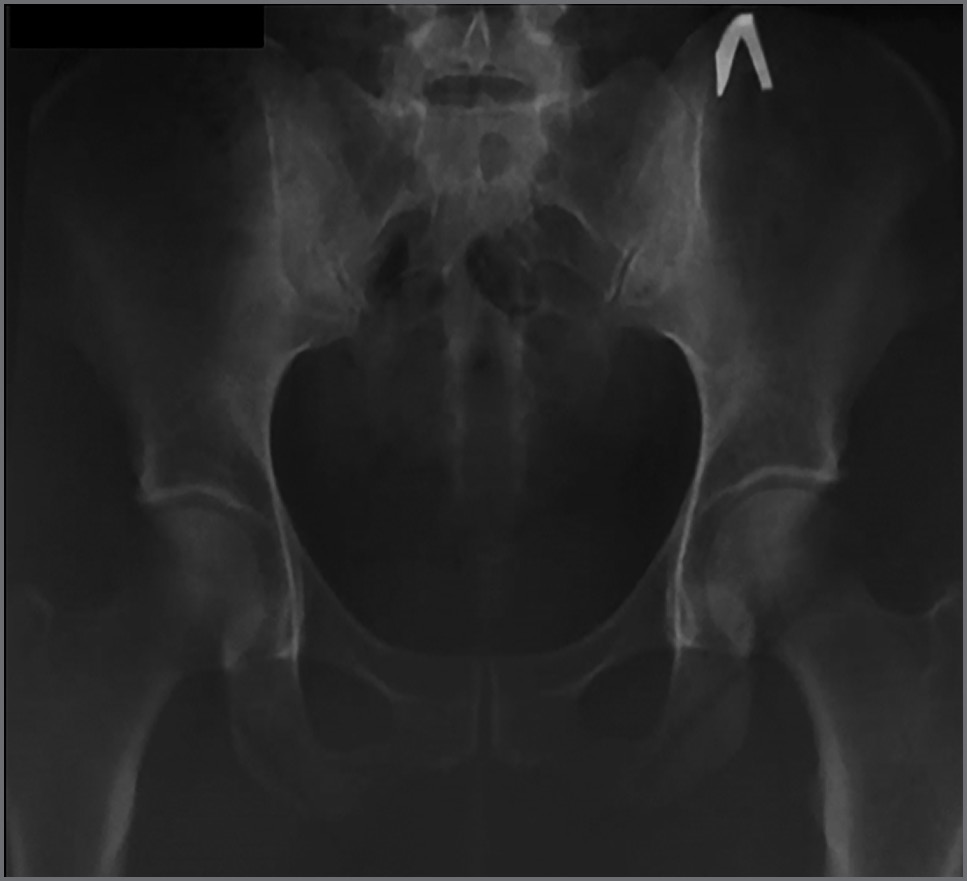

По данным рентгенографии костей таза выявлен двусторонний сакроилиит 2-й степени по Келлгрену (рис. 1).

Рис. 1. Рентгенография костей таза.

Fig. 1. X-ray of pelvic bones.

В описанном нами клиническом случае больной 42 года, однако болей воспалительного ритма в позвоночнике и/или суставах до июня 2020 г. не отмечала. Учитывая, что у пациентки выявлены рентгенологические признаки достоверного сакроилиита 2-й степени по Келлгрену (субхондральный остеосклероз вдоль КПС с двух сторон, сужение и местами расширение суставных щелей) и наличие HLA-B27 гена, АС развивался уже в течение некоторого времени до клинической манифестации, так как остеосклероз КПС формируется обычно в течение нескольких лет. При отсутствии жалоб и объективных симптомов у пациентки со стороны опорно-двигательной системы до 2020 г. новая коронавирусная инфекция COVID-19 могла быть триггером развития классической клинической картины АС.